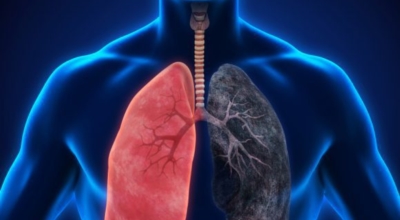

폐암 원인

폐암의 공통 위험요소로 손꼽히는 이유가 되는 것으로 흡연이 있답니다. 흡연자는 비흡연자에 견주어 십몇 배는 더 폐암 발병확률이 높다고 하며 어느정도 기간 동안 흡연했는지에 따라 폐암 발생확률은 더더욱 더 높아져요. 흡연자라고 해도 금연을 하게 되면 폐암 발병확률이 가파르게 내려간다고 하니 폐암이 걱정되신다면 가장 먼저 금연은 필수입니다. 간접흡연 외에도 공사장과 같은 곳에서 미세먼지나 석면, 비소, 라돈, 카드뮴 등 신체에 옳지 않은 성분에 노출되는 환경적 요인으로 폐암이 발병할 수 있다고 하며 유전적 요인으로도 폐암이 발병할 수 있다고 하죠. 가족 중 폐암을 앓았던 분들이 있다면 그렇지 않은 분들에 비교해 2배 가량 더 폐암에 걸릴 확률이 높다고 하는데요 이렇듯 폐암은 나도 모르는 새에 발병할 수 있으므로 자신의 신체 컨디션를 수시로 체크하여 폐암을 초기에 발견하는 것이 현명해요.